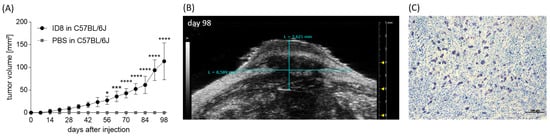

3.3. Optimization of an In Vivo Model to Study the Participation of MCs in Ovarian Cancer Growth

3.4. MC Absence Enhances In Vivo Ovarian Carcinoma Tumor Growth